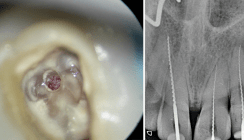

Zugang

Nachdem die Voraussetzungen für eine endodontische Behandlung erfüllt sind, muss der Behandler den idealen Zugang zur Pulpa planen. Die diagnostischen Aufnahmen sind dafür unerlässlich. Die Pulpenkammer ist sehr zentral in der Mitte des Zahnes, sodass ihr Erreichen keine großen Schwierigkeiten verursacht. Der Zugang sollte so gewählt werden, dass ein Maximum der Zahnsubstanz erhalten bleibt und trotzdem ein gerader Zugang zum Pulpengewebe gewährleistet ist. Die Identifizierung und Reinigung solcher Wurzelkanalsysteme ist mithilfe eines Dentalmikroskops einfacher möglich. Die Vergrößerung und die optimale Ausleuchtung lassen die Strukturen besser erkennen und anatomisch zuordnen.

Schnell kann durch die schwierige Konfiguration die Orientierung verloren gehen, sodass eine Messaufnahme sinnvoll wird. Aus Erfahrung ist meist der mesiale Bereich schwieriger bis zum Apex hin zu erreichen als der distale.